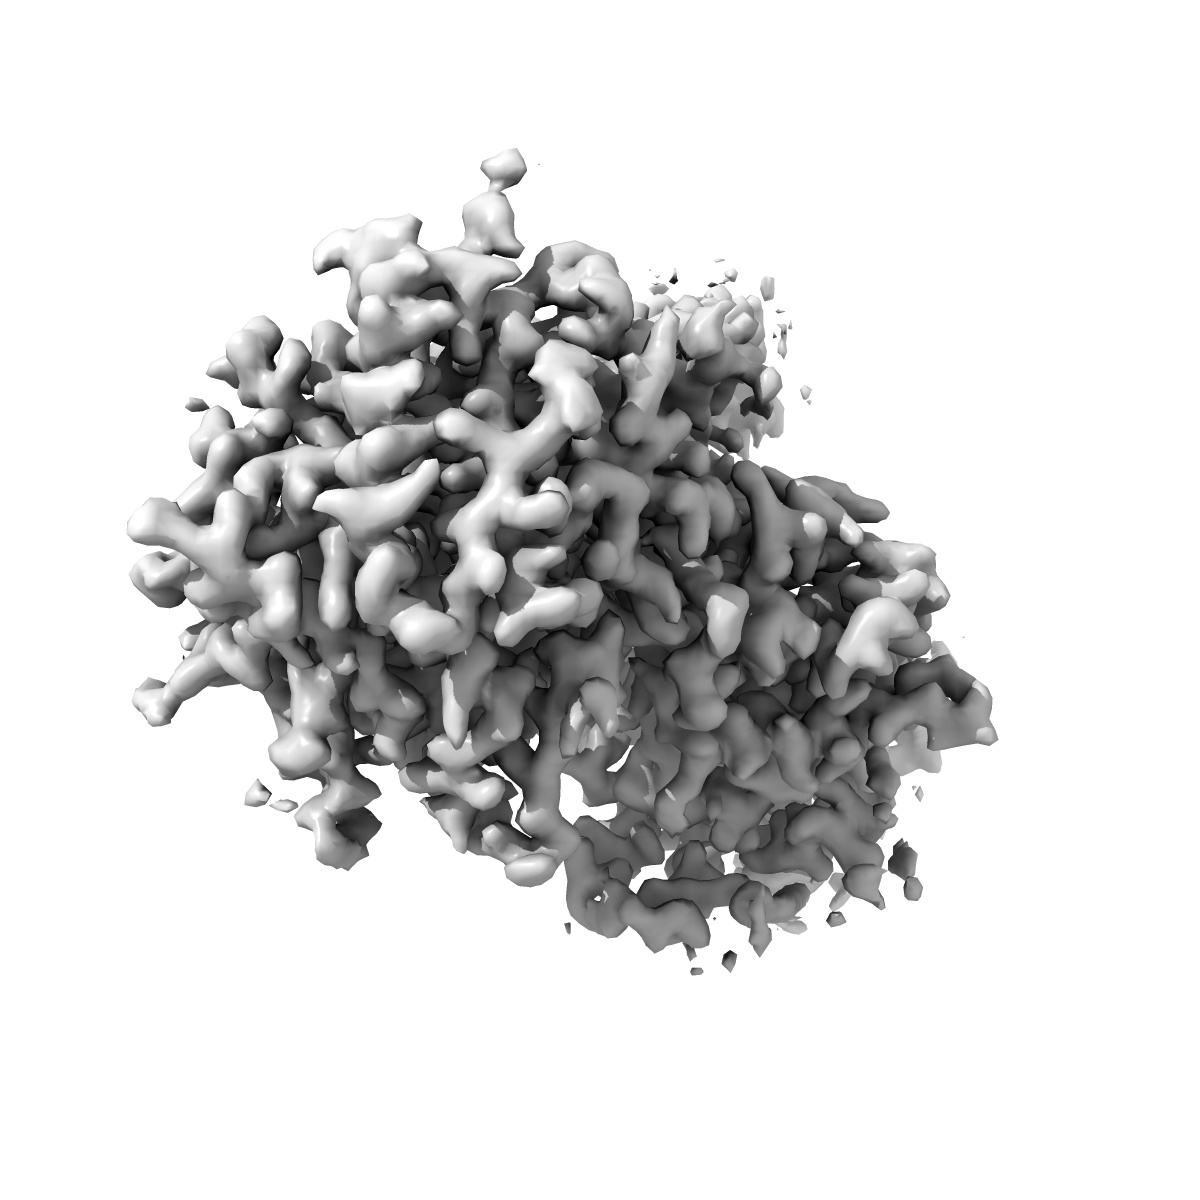

Cryo-EM structure of human gamma-secretase in complex with Nirogacestat

Single-particle2.6 Å

Sample: Cryo-EM structure of human gamma-secretase in complex with Nirogacestat

Structural basis of human gamma-secretase inhibition by anticancer clinical compounds.